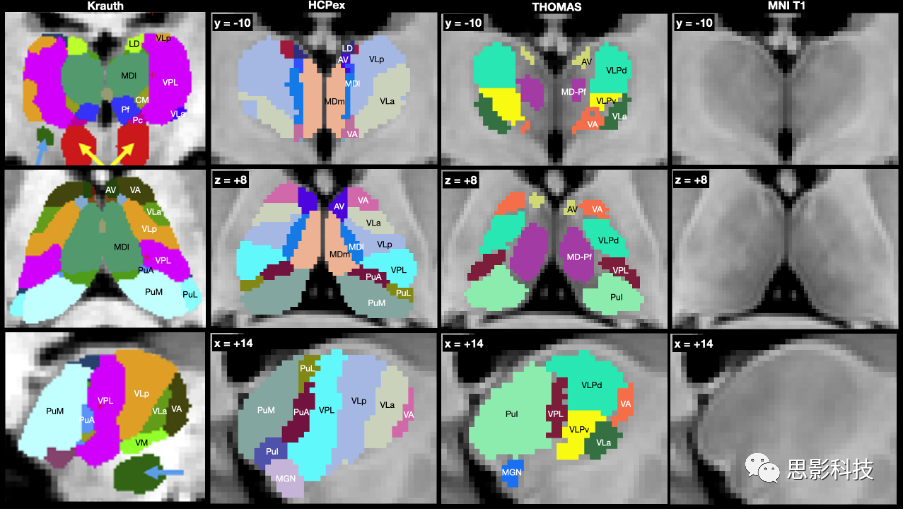

Iglesias et al.(2018)提供的丘脑细分使得HCPex图谱中每个半球包括21个丘脑核团,并因此被优先使用,而不是Tian et al.(2020)提供的只有8个丘脑核团的图谱。从Iglesias et al.(2018)采用的丘脑细分已通过使用基于人脑组织学的Krauth et al.(2010)图谱进行了验证,如补充材料中所描述的(图S1)。作为进一步的验证,采用白质消除MP-RAGE成像技术,将丘脑分割为12个核团的Thalamus Optimized Multi Atlas Segmentation(THOMAS)图谱中的人类丘脑核团也显示在图S1中(Su et al. 2019)。

HCPex图谱中提供的丘脑细分验证 Iglesias等人(2018)提供的丘脑细分使HCPex图谱每个半球包括21个丘脑核团,并因此被优先使用,而不是Tian等人(2020)提供的只有8个丘脑核团的图谱。从Iglesias等人那里采用的丘脑细分已通过使用基于人脑组织学分析的Krauth等人(2010)图谱进行验证,并且如图S1所示,HCPex的分区与之很好对应。为了进一步验证,还展示了图S1中的Thalamus Optimized Multi Atlas Segmentation(THOMAS)图谱中的人类丘脑核团,该图谱使用白质消除MP-RAGE成像技术将丘脑分割成12个核团(Su等人,2019)。

图S1. 使用Krauth等人(2010)的基于组织学的人类丘脑图谱验证HCPex图谱中的丘脑细分。作为比较,还展示了使用白质消除MP-RAGE成像技术将丘脑分割为12个核团的Thalamus Optimized Multi Atlas Segmentation(THOMAS)图谱中的人类丘脑核团(Su等人,2019)。右侧是丘脑的T1图像。

顶部行展示冠状视图;中间行水平视图;底部行展示矢状视图,标有y、z和x的MNI坐标。Krauth等人(2010)的图谱是组织学的,并没有MNI坐标。缩写在表1中展示。